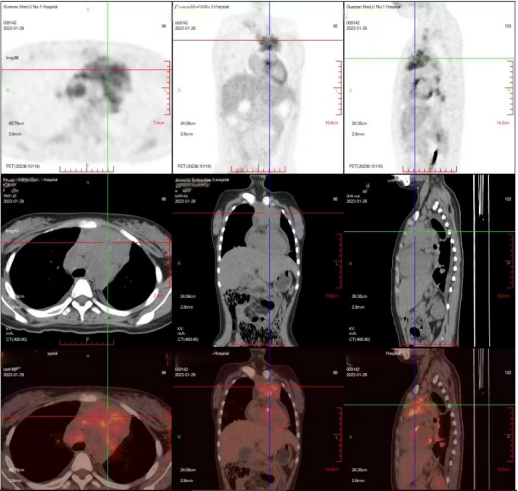

近期,我院肝胆外科成功开展了广西首例精准超声电磁导航穿刺系统引导下肝肿瘤消融术。患者韦某,因上腹部不适半月到我院就诊,...